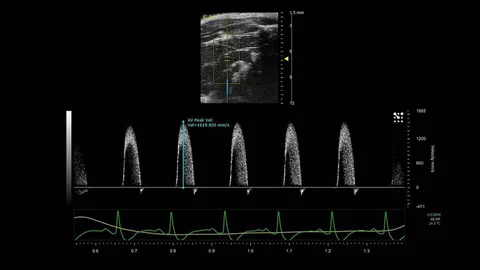

• Pulsed Doppler Ultrasound

Pulsed Doppler Ultrasound

Don Baker, Dennis Watkins, and John Reid designed pulsed Doppler ultrasound technology. Doppler uses the Doppler principle that moving objects change the characteristics of sound waves. By sending short and quick pulses of sound, it becomes possible to accurately measure the velocity of blood in a precise location and in real time.